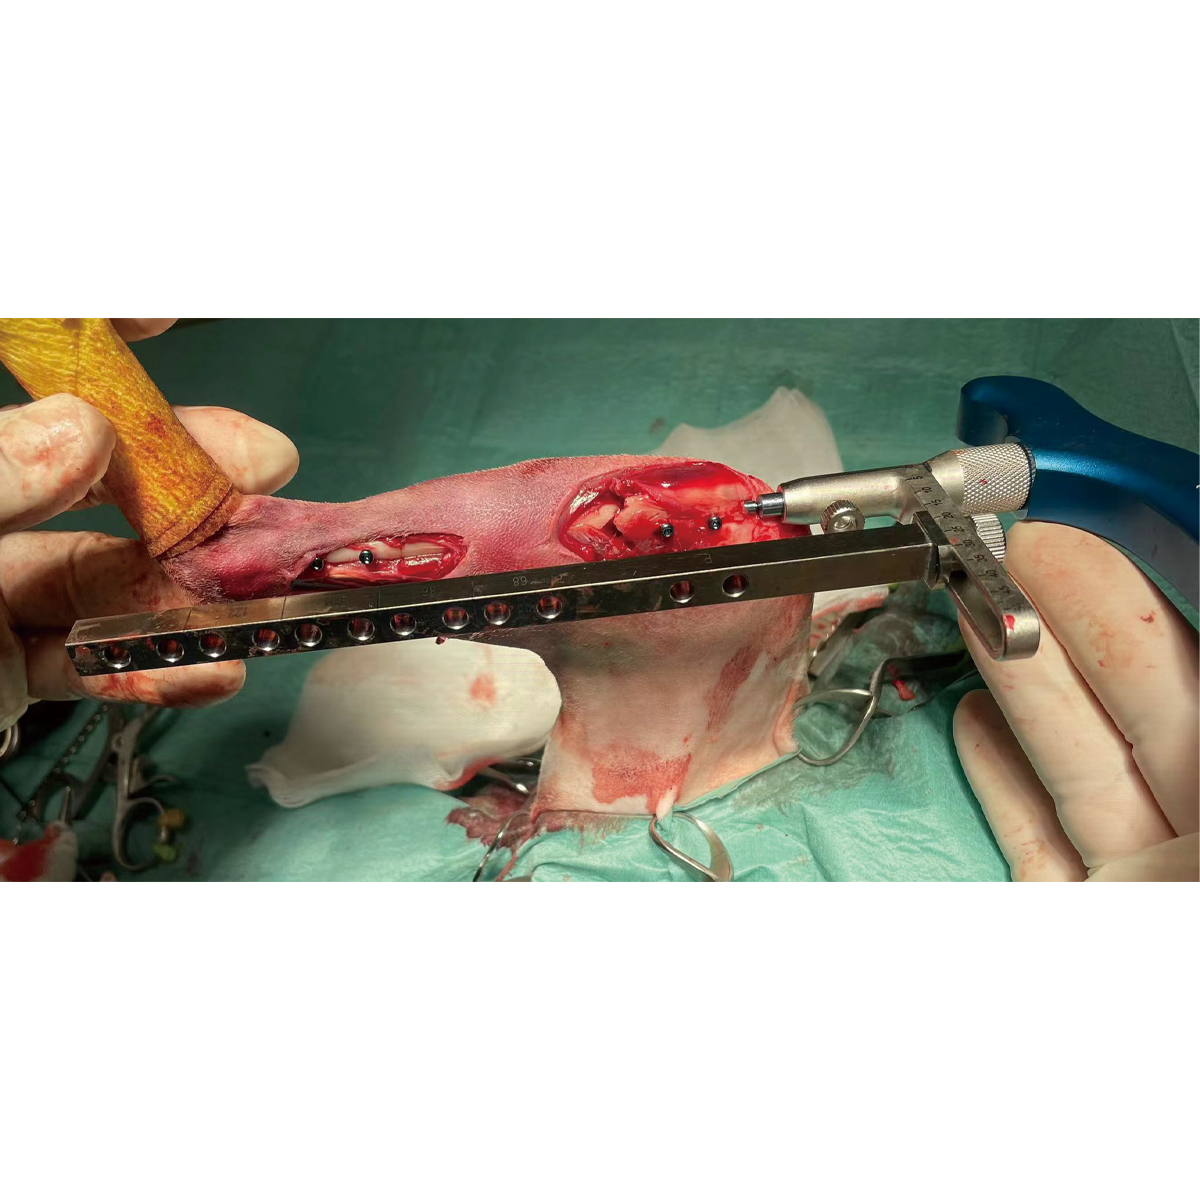

Aiming Device For Interlocking Nail

Guiding Rod For Aiming Device

Screwdriver For Locking Bolt T6

Reamer For Proximal End

Sleeve For Temporary Position Pin

Protection Sleeve For Intramedullary Reaming